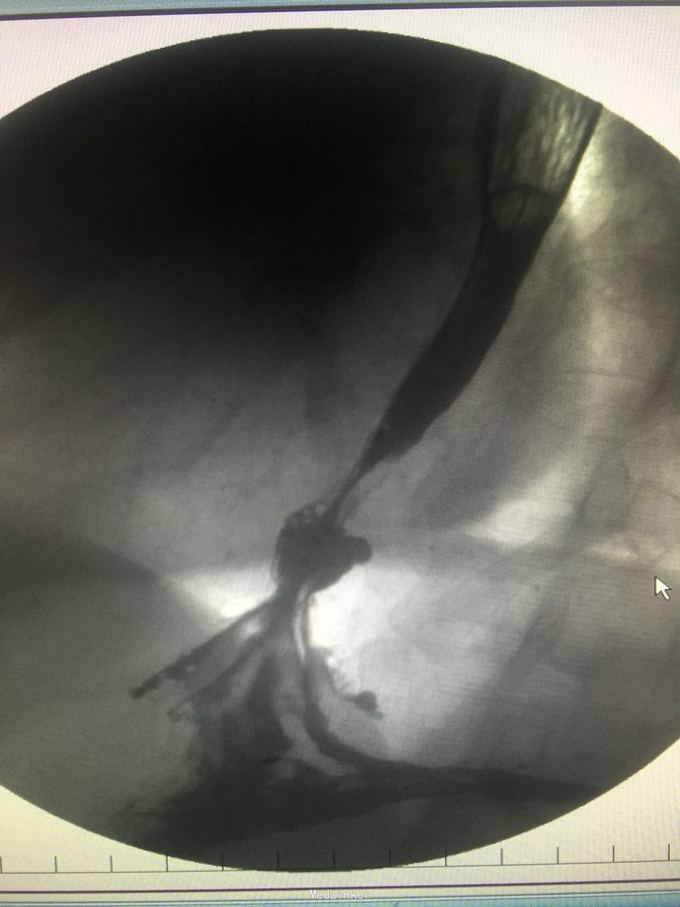

查体无明显异常。 入院检查:胃镜提示反流性食管炎B级、食管裂孔疝、胃炎伴胆汁反流、十二指肠球炎;食管测压:下食管括约肌压力低于正常、食管裂孔疝、食管体部蠕动功能减弱;PH-阻抗:胃食管病理性反流;上消化道造影:滑动性食管裂孔疝、胃食管反流、胃炎。冠脉CTA:前降支中段支架结构完整,管腔通畅,右冠状动脉近段钙化斑块,管腔轻度狭窄。

诊断:胃食管反流病、反流性食管炎、食管裂孔疝、高血压病、冠心病、食管平滑肌瘤切除术后、咽部鳞状细胞乳头状瘤切除术后、胃炎; 处理:已行腹腔镜下食管裂孔疝修补术和胃底折叠术,术后平躺未再出现反酸、反食、呛咳、胸痛。